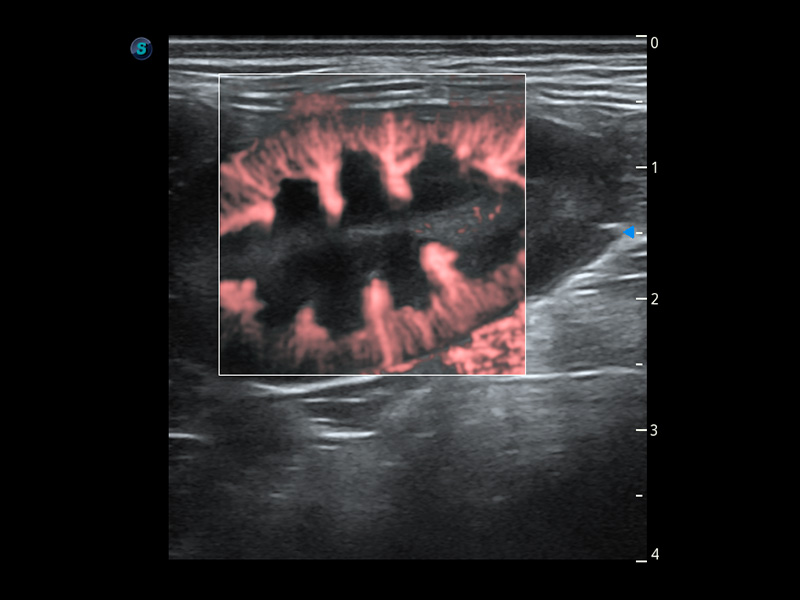

ProPet 60 作为一款高端台式动物超声设备,为动物医生的日常诊断提供了一系列贴合动物临床需求、解决临床实际问题的高级成像功能。凭借全系列高清探头,满足医生对腹部、心脏、生殖、浅表、肌骨等成像的所有需求,切实帮助您提升检查效率,提高诊断信心。